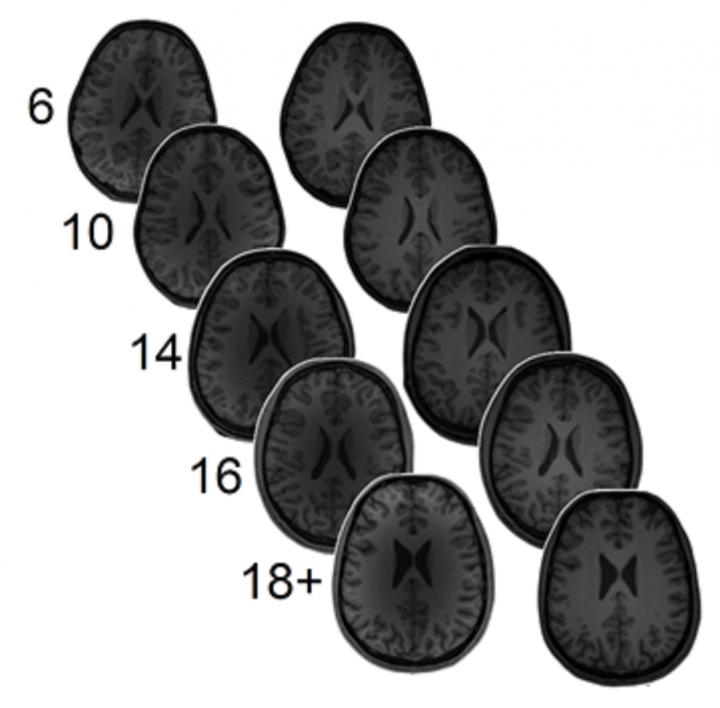

Levels of brain excitement/inhibition are thought to be related to learning, especially during critical periods. However, little is known about how they are related to complex learning that can take place over decades. To address this issue, the researchers measured the levels of GABA and glutamate in 255 people, ranging from 6-year-olds to university students. The participants also took two math achievement tests, and their performance on the arithmetic problems were correlated with the GABA and glutamate levels.

The team found that among young people, higher GABA levels in the left intraparietal sulcus of the brain (a fold in the top, left, back part of the brain) were associated with greater math fluency, while the reverse was true for glutamate. In adults, the results were almost exactly opposite; low GABA concentrations were related to greater math fluency, and again, the reverse was true for glutamate. Because the participants were tested twice about 1.5 years apart, the researchers were also able to show that neurotransmitter levels at the time of the first test could predict math achievement at the later date.